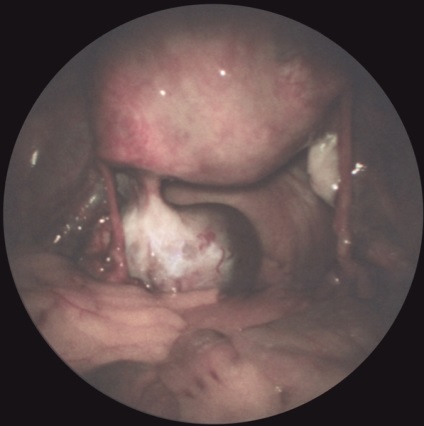

Az első lépés a bevezetése pneumoperitoneum L. a. A hasat kilyukadt egy speciális tű (a tű típusától Leriche) a bal alsó pont nyomkövetés (ábra. 1). A hasüreget adjuk 3000-4000 cm3 levegőt. dinitrogén-oxid vagy szén-monoxid. Attól függően, hogy a célkitűzések a tanulmány beadásra laparoszkópon egyik kiválasztott pontok szerinti rendszer felkutatása gyakran fent és bal oldalán a köldök. Szike, hogy egy bőr bemetszést 1 cm. Boncolással a bőr alatti szövet, és a fascia a rectus abdominis. Ezután, a hüvely trokár szúrja a hasfal, a trokár eltávolítják, és ezen keresztül a hüvely kerülnek bevezetésre laparoszkópot. Ellenőrzés a has szakaszosan végezzük jobbról balra, megtekintésekor a jobb oldali csatorna, a máj, obstruktív és mellékvese térben szubdiafragmatikus helyet. bal oldalsó csatornát medencét. Meg lehet változtatni a helyzetét a beteg részletesebb ellenőrzést. A színe, jellege a felület, az alak a test átfedések, hiszen folyadékgyülem lehet beállítani lézió jellege: májzsugor (2A ábra.) Metasztatikus (2b ábra.), Heveny gyulladás (2. ábra, d.) nekrotikus folyamat (ábra. 2, stb), stb A diagnózis megerősítésére biopszia (általában egy defekt). Széles körben használják különböző orvosi eljárásokban L. hasi vízelvezető (3A.), Mikroholetsistostomiya (ábra. 3b), és mások. Lezárását követően laparoskipii laparoskona és extrahálás a hasüregből a gáz eltávolítása után a bőrön sebet lezárjuk 1- 2 öltés.

Laparoszkópia nőgyógyászat diagnosztikai és terápiás lehet előállítani bevezetésével laparoszkóp a hasfalon keresztül, vagy egy bemetszésen keresztül a posterior vaginális boltozatot (culdoscopy). Javallatok sürgősségi tartja az AL a nőgyógyászati gyakorlatban is gyanús petevezeték terhesség. piosalninks, apoplexia vagy petefészek ciszta, méh perforáció, és így tovább. d. A rutinszerűen elvégzett L. (culdoscopy) hosszan tartó kismedencei fájdalom ismeretlen etiológiájú, algomenoree súlyos, nehezen gyógyítható a szokásos orvosi terápiás módszerek gyanúja belső nemi rendellenességek és más szervekben. Contra L. hajtjuk a hasfalon keresztül ugyanazok, mint az L. vállalta, hogy vizsgálatát a hasüregbe. Culdoscopy ellenjavallt a súlyos összenövések pozadimatochnom térben a tumorokat a medence. Laparoszkópos kép savós petefészek ciszta ábrán látható. 4, valamint. Laparoszkópia is végezni néhány terápiás tevékenység: koaguláció és boncolása összenövések (. 4. ábra, b, c), endokoagulyatsiyu heterotopical gócok endometriumbiopszia petefészek punkció retenciós ciszták és mások.

Ábra. 2a). Laparoszkópos képet bizonyos betegségek és patológiás állapotok a hasüreg - SKD cirrhosis.

Ábra. 2d). Laparoszkópos képet bizonyos betegségek és patológiás állapotok a hasüreg - rostos peritonitis.

Ábra. 2d). Laparoszkópos képet bizonyos betegségek és patológiás állapotok a has - zsír elhalása a felfüggesztés a szigmabél.

Ábra. 2c). Laparoszkópos képet bizonyos betegségek és patológiás állapotok a hasüreg - üszkös cholecystitis.

Ábra. 2b). Laparoszkópos képet bizonyos betegségek és patológiás állapotok a hasüreg - máj metasztázis helye.